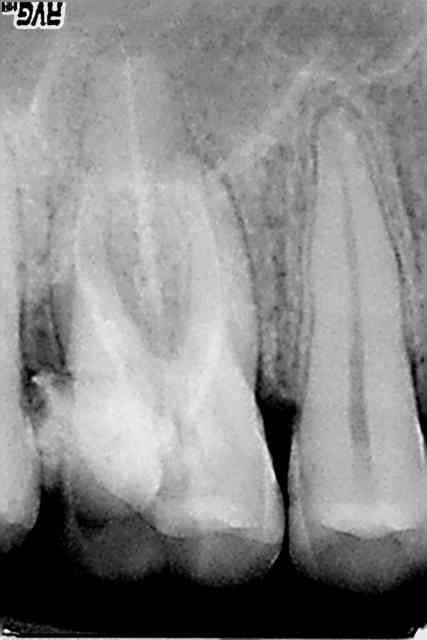

rte sur 16 au r25 un bonheur, le mv2 était imperméable au sx et s1 le r25 n'en a fait qu'une bouchée!

> rte sur 16 au r25 un bonheur, le mv2 était imperméable au sx et s1 le r25 n'en a

> fait qu'une bouchée!

C'est vrai, mais attention quand tu commences à faire des rte au reciproc tu te mets forcément à forcer un peu. La plupart du temps ça marche, et puis parfois ça fait de belles perfos !

Je ne l'utilise plus qu'au niveau apical sur les rte pour débloquer certaines situations.